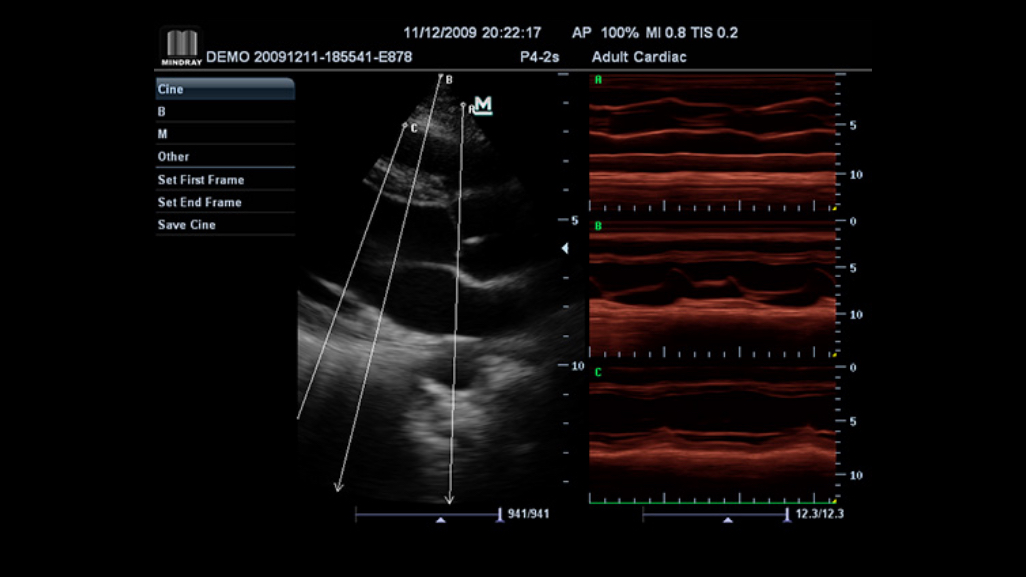

M7 Premium

Overview

Award winning portable hand-carried color Doppler, M7 premium is a High level system with excellent performance. Equipped with dedicated cardiac package and easy-to-use workflow software, M7 premium offers an ideal packaged solution to address the needs of cardiologists.